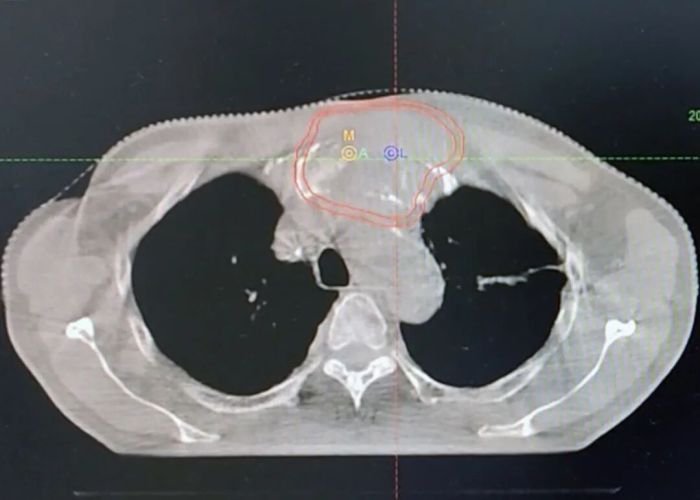

刘先领院长精准提出两步走策略:一方面,为尽快控制局部病情,在等待“泛癌种NGS检测”结果期间,先行对胸骨转移瘤进行放射治疗;另一方面,计划在此后进行穿刺,联合病理科开展更为精细的免疫组化分析。

随后的诊疗进程验证了这一思路的高效性,放疗及时稳定了局部病情,而进一步的病理检测带来了关键发现:患者PD-L1表达呈极高水平(CPS评分90)。